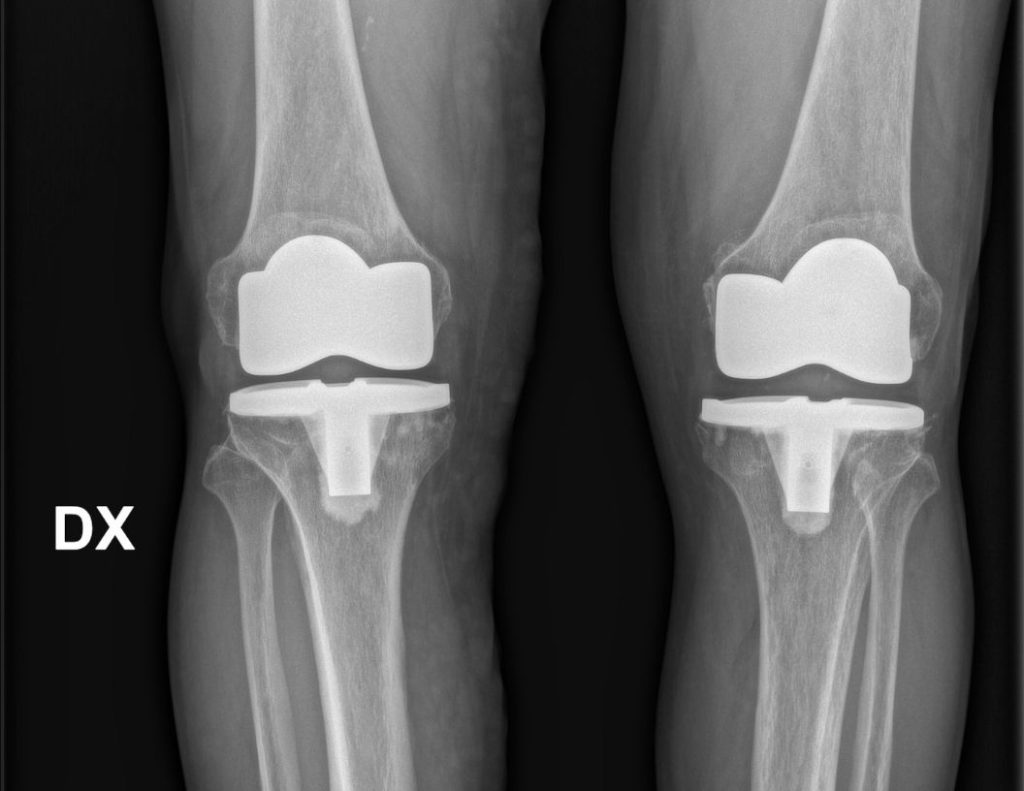

gonartrosi bilaterale

dopo